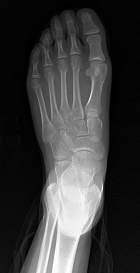

R.T. - 15 year old female noticed left dorsal foot mass two months ago; it is slightly tender to touch and bothers her with full plantar flexion, she also noticed some discoloration of the skin in the area

Zoom image: Radiological image Radiological image.